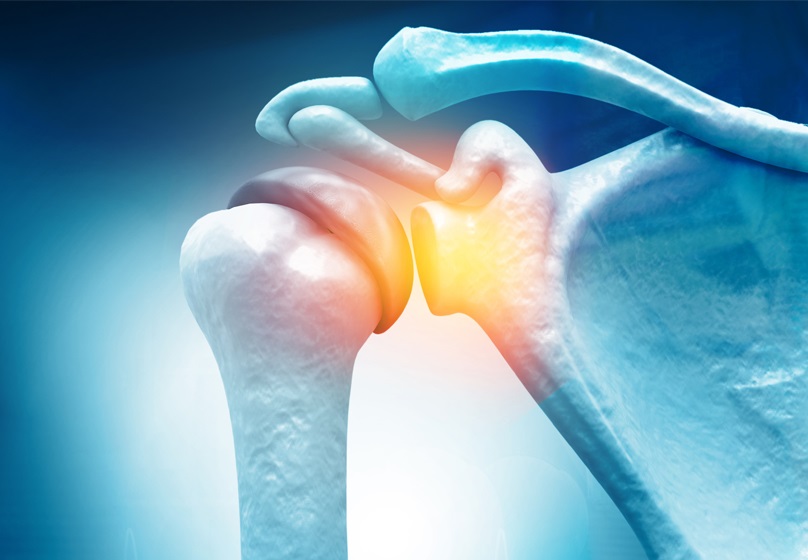

Αρθροπλαστική ώμου με Σύστημα Πλοήγησης Επαυξημένης Πραγματικότητας

Τα τελευταία χρόνια στην ορθοπαιδική χειρουργική έχουν παρουσιαστεί διάφορα συστήματα (ρομποτικά, πλοήγησης) με σκοπό τη βελτίωση της χειρουργικής ακρίβειας και την εξατομίκευση στην τοποθέτηση των αρθροπλαστικών - της αντικατάστασης δηλαδή των αρθρώσεων του ισχίου και του γόνατος.

Η τεχνολογία αυτή, πρόσφατα, αναπτύχθηκε και για την άρθρωση του ώμου, για την υποβοήθηση του Χειρουργού κατά τη διενέργεια της αρθροπλαστικής ώμου, επέμβαση που αντικαθιστά την άρθρωση.

«Η αρθροπλαστική ώμου είναι μια χειρουργική μέθοδος κατά την οποία η άρθρωση αντικαθίσταται από προθέσεις που αποτελούνται από ειδικά κράματα μετάλλων και πολυαιθυλένιο», αναφέρει ο κ. Γεώργιος Φλεβαράκης Ορθοπαιδικός Χειρουργός, Αναπληρωτής Διευθυντής της Γ’ Ορθοπαιδικής Κλινικής – Κλινικής Χειρουργικής Ελάχιστης Επεμβατικότητας (MIS) του Metropolitan General και συνεχίζει:

Πότε ενδείκνυται η αντικατάσταση της άρθρωσης του ώμου;

Η άρθρωση του ώμου μπορεί να φθαρεί τόσο από παθήσεις, όσο και από τραυματισμούς όπως:

- Η αρθρίτιδα του ώμου

- Τα κατάγματα

- Οι χρόνιες ρήξεις τενόντων

- Η οστεονέκρωση της κεφαλής

Στις περιπτώσεις αυτές διαταράσσεται η λειτουργία της άρθρωσης και εγκαθίσταται μόνιμος πόνος. Όταν τα συντηρητικά μέτρα δεν επαρκούν για βελτίωση της κατάστασης ενδείκνυται η αρθροπλαστική.

Ποια είδη αρθροπλαστικής ώμου υπάρχουν;

- Η ανάστροφη αρθροπλαστική ώμου η οποία είναι η πιο διαδεδομένη

- Η ανατομική αρθροπλαστική

- Η αρθροπλαστική επιφανείας

- Η ημιαρθροπλαστική

Οι 3 τελευταίες χρησιμοποιούνται πλέον σπάνια και κυρίως σε νεότερους ασθενείς.

Τι είναι η Ανάστροφη αρθροπλαστική ώμου;

«Η ανάστροφη αρθροπλαστική ώμου είναι πλέον η πιο συχνή μέθοδος αντικατάστασης της άρθρωσης του ώμου, η οποία διαφέρει από την κλασική αρθροπλαστική ως προς τον σχεδιασμό, καθώς έχει “ανάποδο” σχήμα, γι’ αυτό και ονομάζεται ανάστροφη αρθροπλαστική.

Ειδικότερα, στην επέμβαση της ανάστροφης αρθροπλαστικής η κεφαλή του βραχιονίου αντικαθίσταται με μια κοίλη επιφάνεια. Από την άλλη, η ωμογλήνη αντικαθίσταται με μισή σφαίρα.

Με αυτόν τον τρόπο, επιτυγχάνεται καλύτερη και ανώδυνη κίνηση στις περιπτώσεις που ο ώμος πάσχει από βαριά αρθρίτιδα με κατεστραμμένους ή ανεπαρκείς τένοντες ή μετά από συντριπτικά κατάγματα της κεφαλής. Αυτές είναι περιπτώσεις στις οποίες δεν θα λειτουργούσε καμία άλλη κλασική χειρουργική μέθοδος», επισημαίνει.